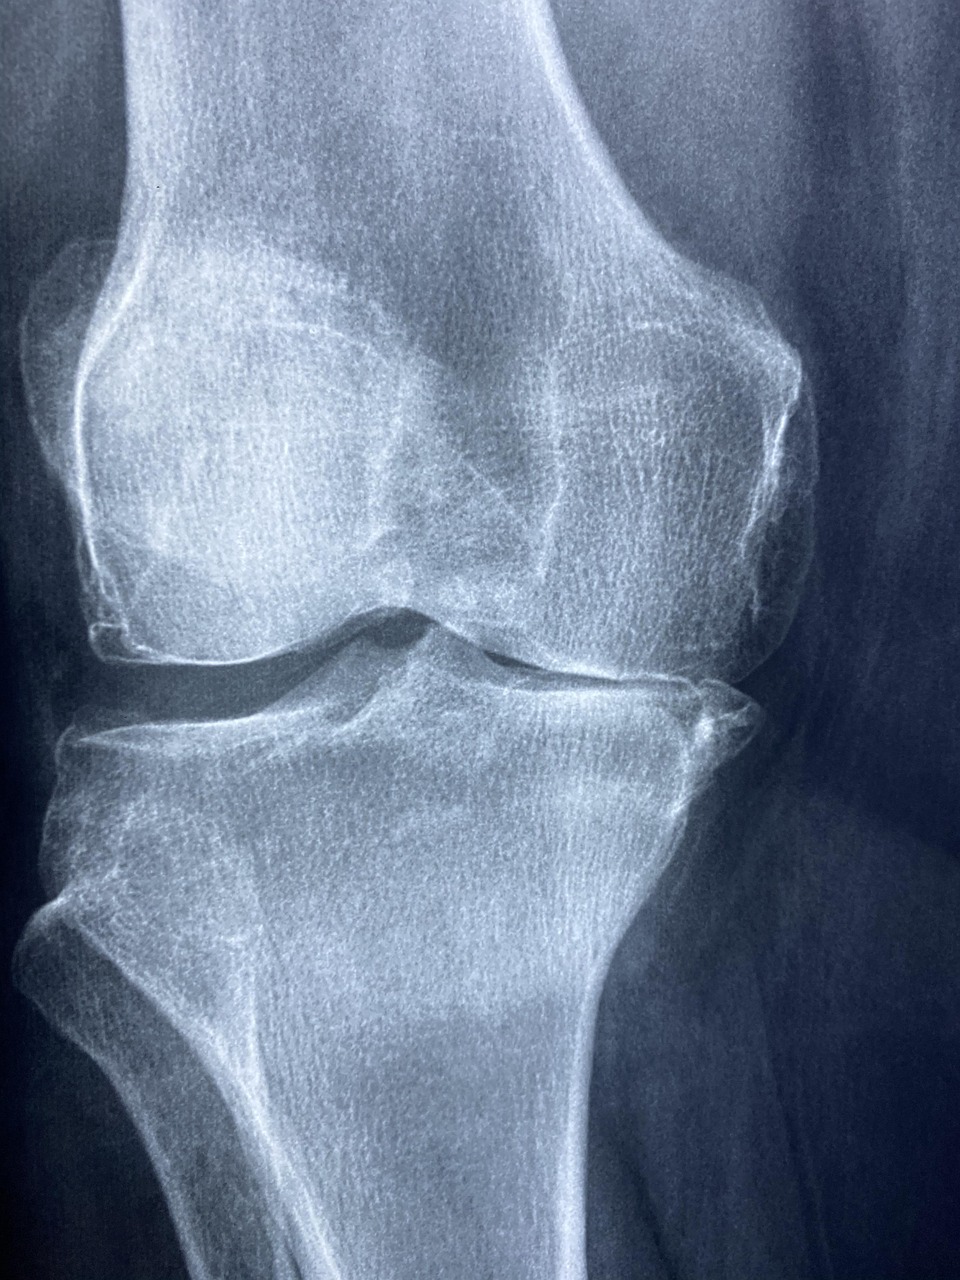

저도 주변에서 “어제는 괜찮았는데, 어느 순간 계단 내려갈 때 무릎이 시큰거리더라” “병원 가니 연골이 생각보다 많이 닳았다고 하더라” 이런 말을 정말 자주 듣습니다.

문제는, 연골은 한 번 닳으면 재생이 거의 안 된다는 것입니다.

왜 50대 이후 연골이 급격히 닳을까?

그 이유는 단순합니다. 나이가 들수록 연골 구성 성분이 감소하기 때문입니다.

- 연골 내 콜라겐 감소

- 관절 윤활 역할을 하는 히알루론산 감소

- 염증 반응 증가

- 연골 재생 세포 활성이 20대 대비 50% 이하로 감소

즉, 쓰는 속도 > 재생 속도가 되면서 통증·뻣뻣함·소리·붓기 등이 나타납니다.